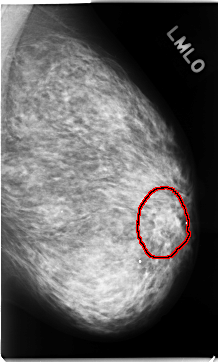

C_0130_1.LEFT_CC

LEFT_CC LINES 4752 PIXELS_PER_LINE 2704 BITS_PER_PIXEL 12 RESOLUTION 50 OVERLAY

FILE: C_0130_1.LEFT_CC.OVERLAY

TOTAL_ABNORMALITIES 1

ABNORMALITY 1

LESION_TYPE MASS SHAPE OVAL MARGINS ILL_DEFINED

ASSESSMENT 4

SUBTLETY 3

PATHOLOGY MALIGNANT

TOTAL_OUTLINES 1

BOUNDARY